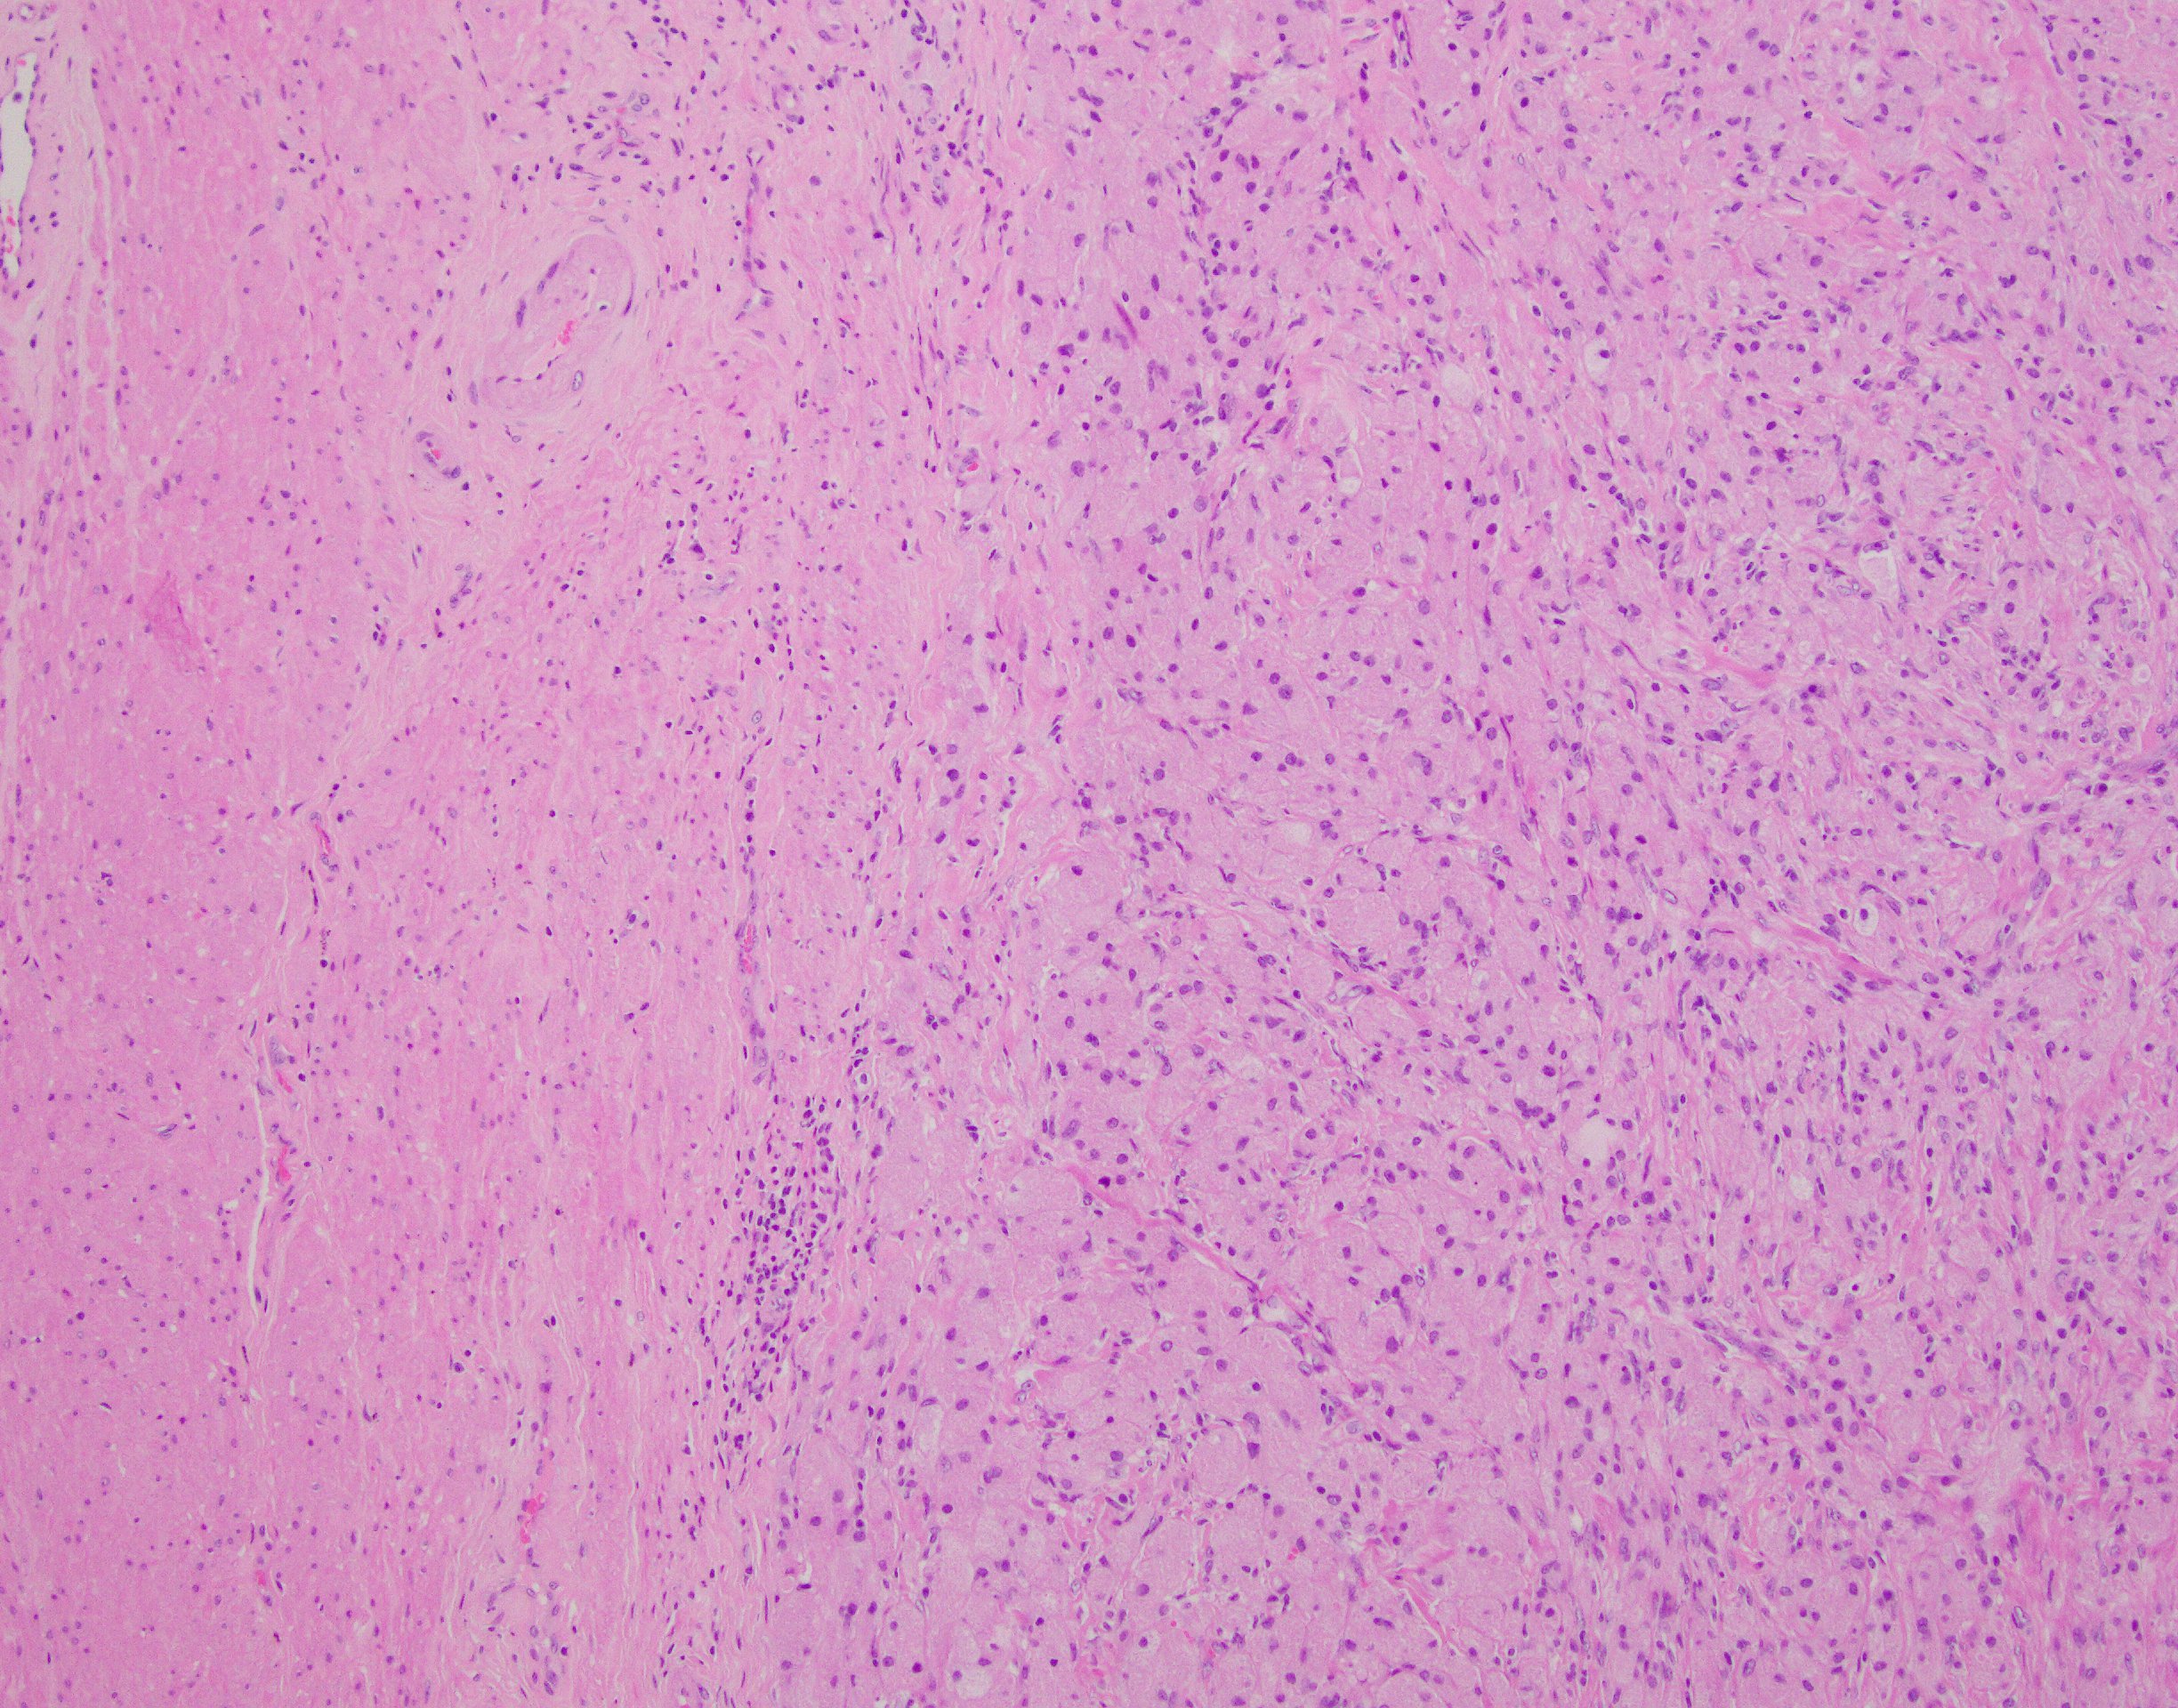

29-year old male with a 4.7 cm gastric mass. The immunoprofile of this tumor is CD117 -, DOG1 -, Sox10 + and CD68 +.

The answer is “C”, Granular Cell Tumor (GCT) (Example “A”, Granular cell tumor)

Granular cell tumors from the GI tract are relatively uncommon and comprise approximately 4% to 6% of all GCTs with the stomach GCT being the least common location while esophagus and colorectal being the most common GI tract sites. GCTs are neural crest derived lesions that express both S100 and Sox10 in addition to lysosomal markers such as CD68 (the lesional cells’ cytoplasm is packed with these structures giving them their characteristic appearance). The exceedingly rare examples of GCT might show a combination of the following features:  highly infiltrative borders, necrosis, spindling, high N:C ratio, vesicular nuclei with large nucleoli, nuclear pleomorphism,  increased mitotic activity (more than 2 mitoses/10 high-power fields) and/or increased proliferative index by Ki-67 (> 10%). None of these features were present in the presented case.